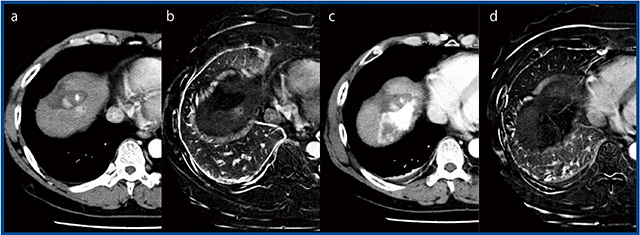

症例1は,51歳,男性の肝細胞がんで,TACE併用RFAを施行した(図1)。RFA前の造影CTでは以前TACEを行った後にできた新しい病変を描出しているが(図1 a),TACE併用RFA後ではリピオドールの残存が高吸収域となっており治療効果を判定できない(図1 c)。このような場合にSURESubtractionを用いることで,腫瘍が焼灼されたことを明瞭に確認できる(図1 d)。

図1 症例1:肝細胞がん(51歳,男性)

a:造影CT画像(TACE併用RFA前) b:SURESubtraction(TACE併用RFA前)

c:造影CT画像(TACE併用RFA後) d:SURESubtraction(TACE併用RFA後)